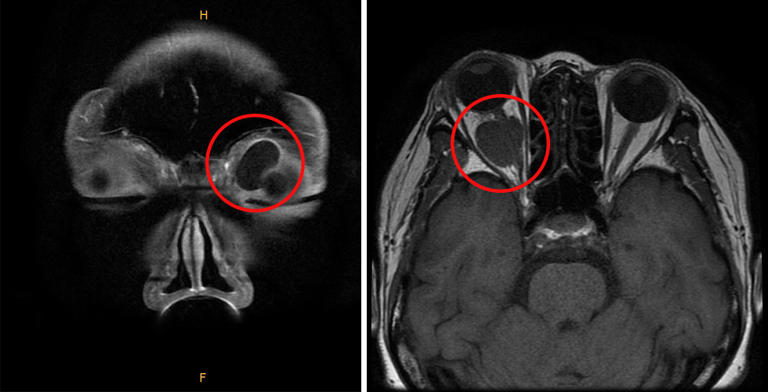

몸 곳곳에 종양이 생길 수 있다는 사실은 알지만, 눈에도 발생할 수 있다는 건 모르는 사람이 많다. 특히 눈을 둘러싼 뼈, 근육, 지방, 혈관, 신경, 눈물샘에 종양이 생길 수 있는데, 이를 '안와 종양'이라 한다.

안와 종양은 크게 악성과 양성으로 분류된다. 악성 종양은 암을, 양성 종양은 암이 아닌 종양을 말한다. 순천향대부천병원 안과 장선영 교수는 "​안와 종양의 악성과 양성을 감별하기 위해 대부분 조직검사를 해야 한다"며 "악성 종양이 아니더라도 시력 저하, 시야 결손 등 기능적 문제뿐 아니라 미용적인 문제를 유발할 수 있어 조기 진단과 함께 적절한 치료를 받는 것이 좋다"고 말했다.

안와 양성 종양은 생긴 위치에 따라 다양한 증상을 유발한다. 시신경 근처에 생기면 시력 저하, 시야 감소 증상이, 안구를 움직이는 근육이나 신경 근처에 생기면 안구운동장애, 복시, 사시 등이 나타난다. 눈물샘이나 안구 뒷부분에 종양이 커지면 안구 돌출이나 눈꺼풀 부종이 생길 수 있다. 그 외 위치에 따라 결막부종, 종괴, 눈꺼풀 처짐이 나타날 수 있다.

안와 양성 종양 종류는 매우 다양하며, 종양에 따라 잘 생기는 연령, 성별도 다양하다. 유피낭종과 표피모양낭종은 안와낭종으로 분류되며, 주로 소아에서 발생한다. 다형샘종은 눈물샘에 생기는 종양으로, 40대 남성에서 흔히 발생한다. 시신경교종은 시신경에 생기는 종양으로 중년 여성에서 많이 나타난다. 그 외에도 수막종, 신경집종, 혈관성 종양인 영아혈관종, 고립섬유종, 해면혈관종 등 다양한 종류가 있다.

안와 종양 진단 방법은 환자의 얼굴을 관찰하고, 만져지는 덩어리가 있는지 확인하며, 덩어리에서 소리가 들리는지 확인하는 식으로 진행한다. 이후 안구돌출계를 이용해 눈에 안구 돌출이 발생했는지 확인한다. 이학적 검사상, 안와 사인이 명백하게 관찰되면 이후 CT, MRI 등 이미지 검사를 시행한다.

안와 양성 종양은 일반적으로 수술을 통해 제거한다. 하지만 발생 위치에 따라 합병증 발생 위험이 있어 신중하게 치료 방향을 결정해야 한다. 먼저 수술 전 CT 및 MRI 검사를 통해 종양의 크기, 위치, 성상을 정확하게 파악하고 분석한다. 안와 앞쪽에 위치한 종양은 상대적으로 쉽게 제거할 수 있다. 흉터 없이 제거하기 위해 쌍꺼풀 라인을 따라 절개하고 수술을 진행할 수도 있다.